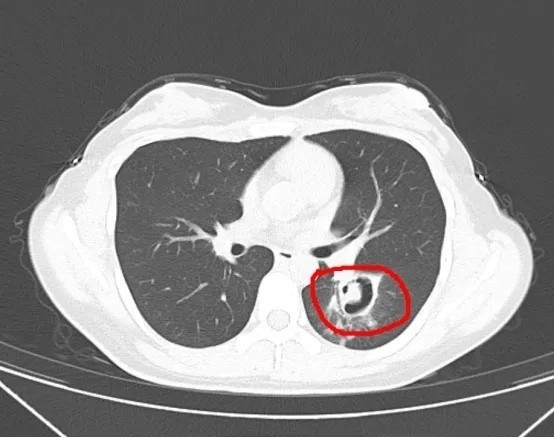

被诊断为霉菌性肺炎

为了进一步确诊病情

医生为她做了纤维支气管镜检查

发现气道壁上缀着大量白色菌斑

化验后确认是曲霉菌